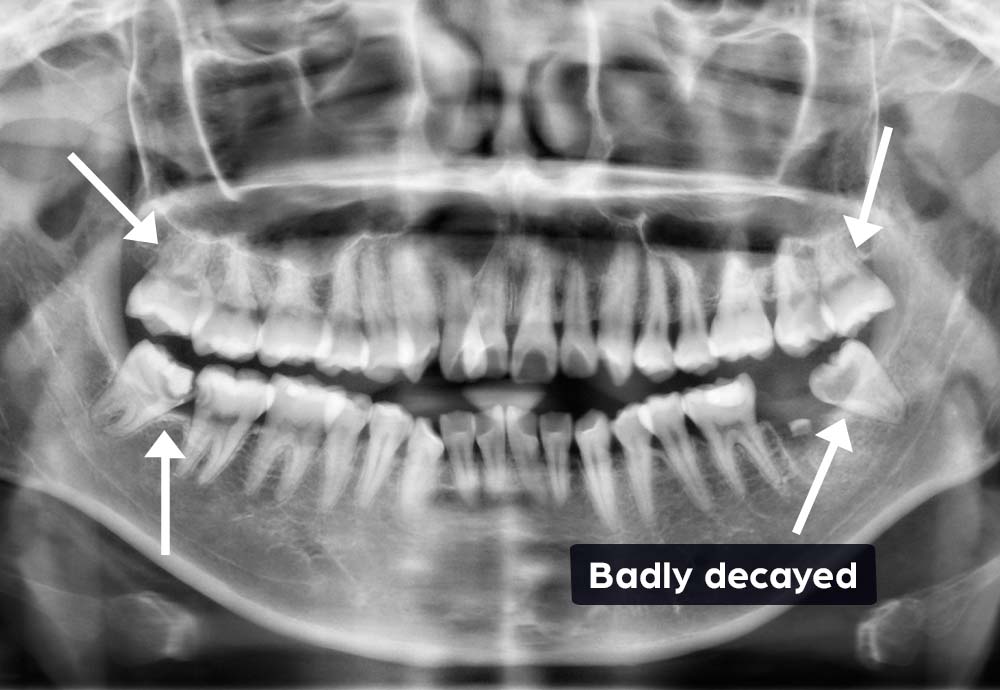

Wisdom teeth may need to be removed if they are impacted, causing pain, swelling, infection, or damage to nearby teeth.

Other reasons include preventing future dental problems such as decay, gum disease, cysts, or crowding of your existing teeth.

“Instead of extraction, I chose root canal therapy because it’s the only molar he has left on this side to chew.”- Dr Karen